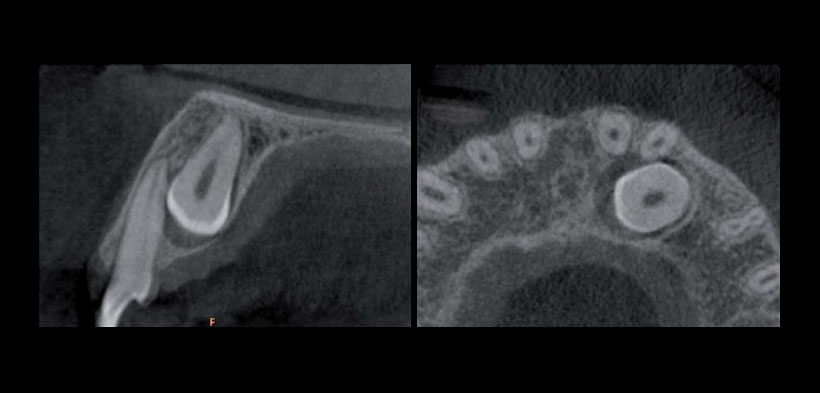

La retención de los caninos puede causar la migración de los dientes adyacentes, pérdida de la longitud y el ancho del arco dentario, y en muy bajas posibilidades la formación de lesiones quísticas, tumores e infecciosas. Sin embargo, una consecuencia importante de la ruta anormal de erupción del canino superior dentro del proceso alveolar dental es la resorción radicular de los dientes adyacentes, comprometiendo la longevidad de estos dientes. Este proceso es a menudo asintomático; por lo tanto, cuando la resorción se diagnostica clínicamente, el proceso puede ser tan avanzada que ya no es posible realizar tratamientos conservadores.

La tomografía computarizada cone beam (CTCB) elimina las limitaciones antes mencionadas, permite la reconstrucción de las estructuras escaneados en diferentes planos, así como reconstrucciones (3D) tridimensionales de alta calidad con una distorsión mínima, costo relativamente bajo, y la dosis de radiación reducida significativamente en comparación con otras modalidades de TC.

Fig. 1. Tomografía computarizada cone beam (CBCT) (A) y axial (B) muestra un canino impactado causando reabsorción radicular leve del incisivo lateral.